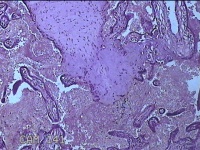

胎盘组织

性别

女

年龄

35岁

临床诊断

胎膜早破 早产

一般病史

停经36+1周,阴道流液3天。

标本名称

大体所见

灰白暗红色胎盘组织18x15.5x2.3㎝一个,表面光滑,血管清晰,颜色发暗,绒毛面结节状,轻度糜烂,表面有少许凝血块,切面见绒毛内有部分淤血,边缘蜕膜可见多个小血肿,脐带15x1.5x0.8㎝,切断脐带,见脐血管内有凝血块。